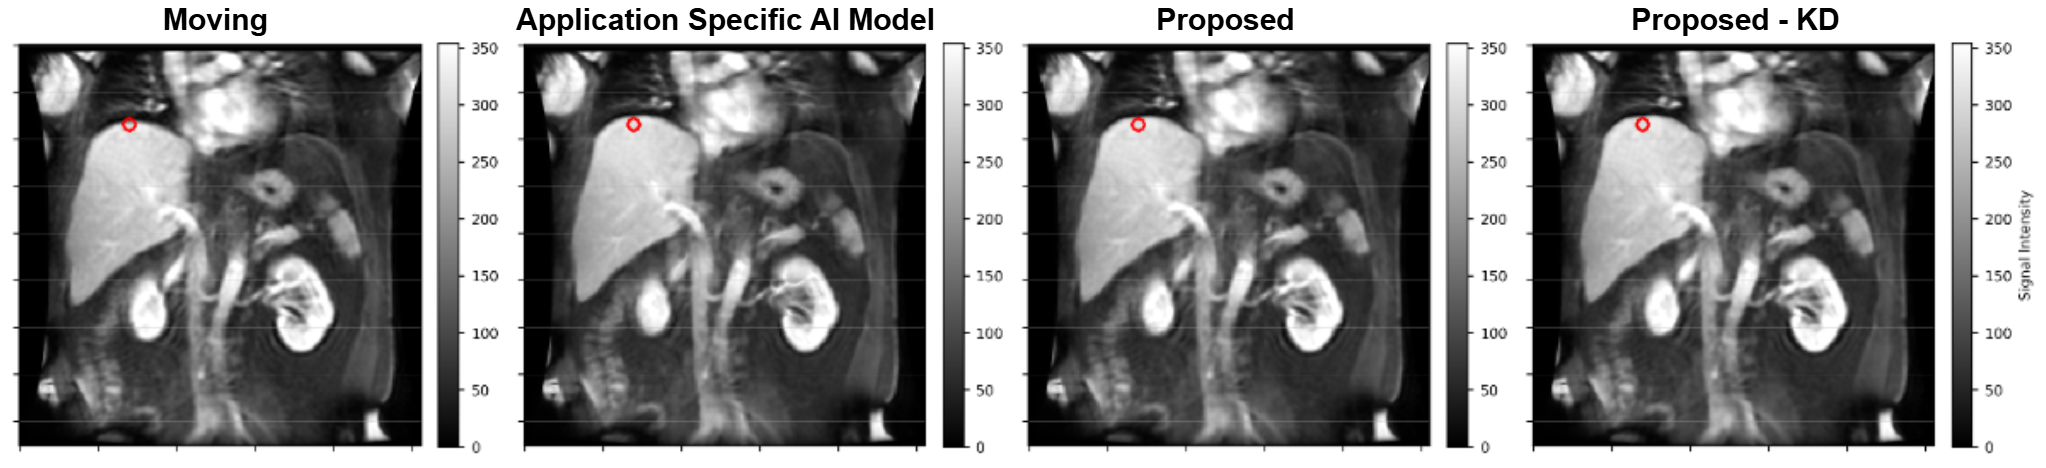

Analysis: To understand the alignment of structures over the temporal frames, the contrast uptake curves are plotted in a region of interest (ROI) at liver dome (region highly susceptible to motion). Additionally, we trained a comparison model, Application Specific AI model, using the same dense teacher network and loss function as the TTO-based approach exclusively for liver DCE-MRI (500 epochs, 261 paired volumes). Achieving comparable performance between this model and the TTO-based method would suggest that TTO maintains structural alignment accuracy while providing enhanced generalizability.

The contrast uptake curves for red ROI in Figure 3(a) are shown in Figure 3(b). The sudden drop and spike in the contrast uptake curve (red) for moving image render them physiologically implausible. Post registration using the proposed method, both DL Reg (green curve) and DL KD Reg (orange curve), have corrected such abberations in the contrast uptake curve. The contrast uptake curves using proposed method matches the contrast uptake curve post correction using the application specific model (blue curve). This shows that the proposed generalizeable method performs as good as an AI model specifically trained for the application (hence, no compromise in performance). The green and orange curve matching each other indicates that the miniaturized KD model performance is equivalent to the dense model. Image alignment post registration was evaluated using PMMs (see Appendix C). Patch-wise normalized MI was computed for the image pairs: (fixed, moving), (fixed, DL Reg), and (fixed, DL KD Reg) on 3D patches of size 16×16×1616\times 16\times 16 voxels with a stride of 4. The PMMs were subsequently averaged across timepoints for each slice to obtain a mean PMM. The mean PMMs for the target slice is shown in Figure 3(c). The aggregated mean PMM values were: fixed–moving = 0.3801, fixed–DL Reg = 0.4291, and fixed–DL KD Reg = 0.4195. The increased values indicate higher alignment post registration. This is evident from increased values in air pockets around the liver, kidney and spleen regions. Visual assessments were also performed by overlaying the image pairs pre- and post registration using the proposed method (refer Appendix D Figure 6).

Figure 3: Left to right for Figure 3(a) show moving, registered using application specific AI model, DL Reg, and DL KD Reg. The contrast uptake curves in Figure 3(b) indicate expected correction post registration. Higher PMM values observed post-registration (Figure 3(c)) indicate improved structural alignment.